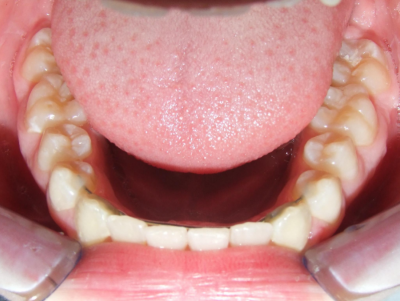

Leeftijd bij aanvang: 10 jaar

Bonded Hyrax + volledig vast onderkaak

Volledig vast bovenkaak + expander

Wrap + c-c bar onderkaak

Leeftijd bij afname: 12 jaar

Voor behandeling

Na behandeling